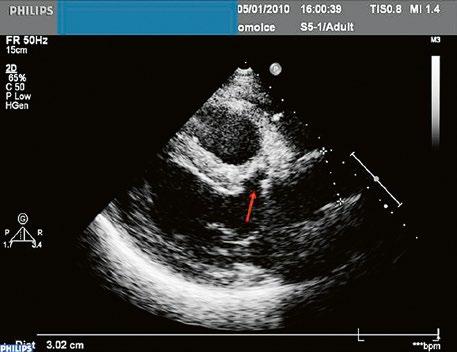

Poslechový nález systolického šelestu nad plicnicí s fixním rozštěpem 2. ozvy je nenápadný. Echokardiograficky je patrná dilatovaná a objemově přetížená pravá komora s paradoxním pohybem septa (Obr. 45.9), zkratový tok může být vidět i transtorakálně (TTE) (Obr. 45.10, Video 45.3, Video 45.7), ale suverénní diagnostickou metodou je jícnová echokardiografie (TEE), případně s 3DE zobrazením (Obr. 45.1, Obr. 45.2,

Obr. 45.9 M mode, paradoxní pohyb septa při objemovém přetížení pravé komory u defektu septa síní typu II s levopravým zkratem